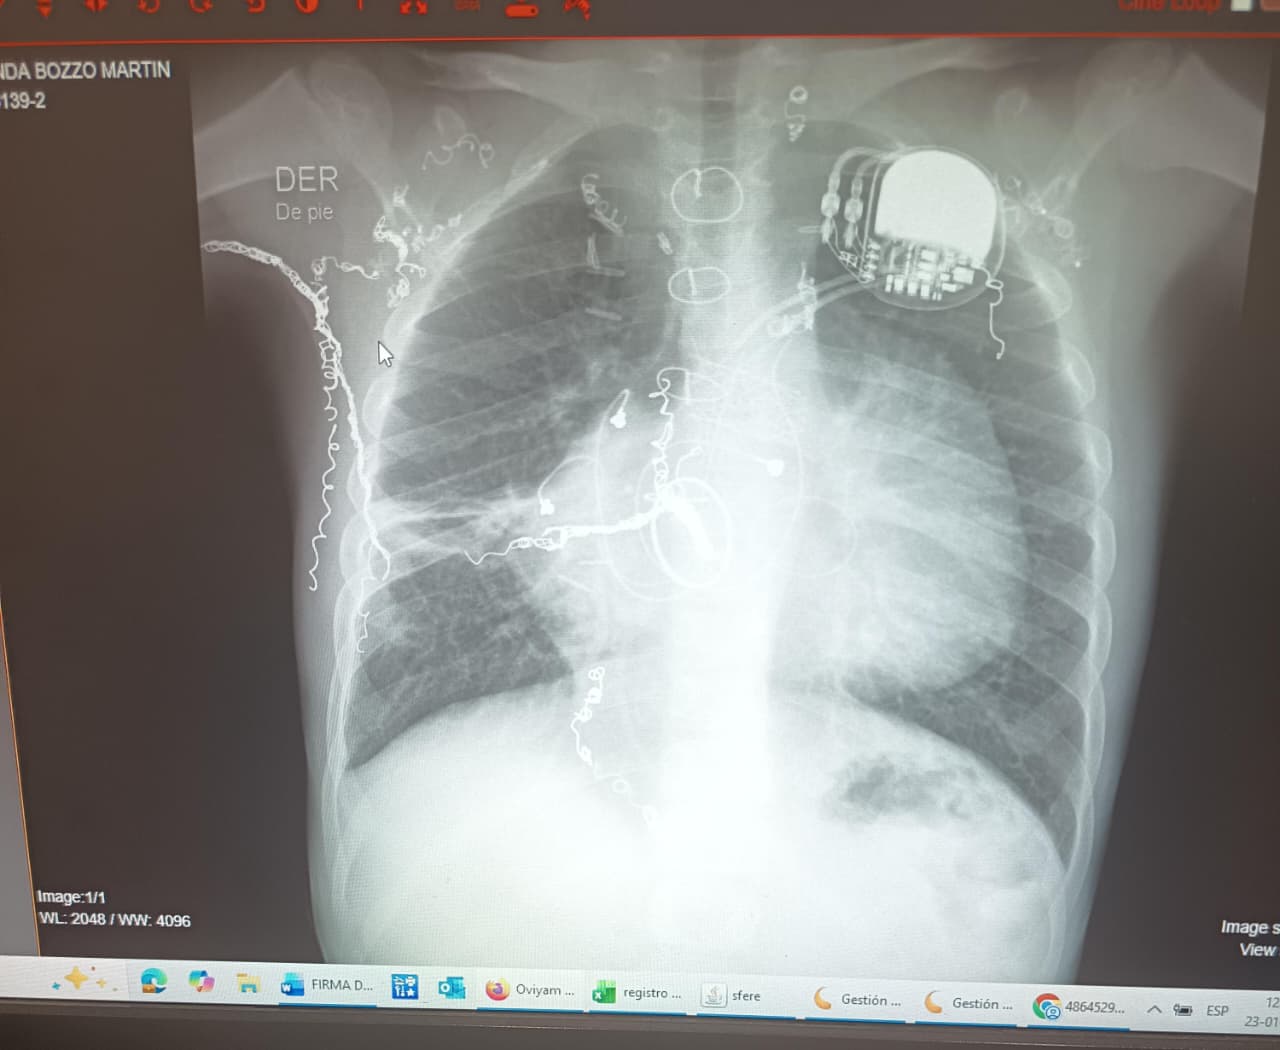

La historia de Martín comenzó en Santiago. Durante sus primeros años fue intervenido en el Hospital Luis Calvo Mackenna, donde enfrentó cinco cirugías a corazón abierto y múltiples cateterismos. Es portador de marcapasos y de una válvula mecánica tricúspide.

Actualmente vive en Viña del Mar. Su hospital base es el Gustavo Fricke y el eventual trasplante se realizaría en la Clínica UC Christus, en Santiago. Pesa 20 kilos y requiere un donante infantil compatible con su tamaño anatómico, condición que reduce las probabilidades y hace más compleja la espera. Debido a su baja saturación de oxígeno, utiliza silla de ruedas para desplazarse largas distancias y se fatiga con facilidad. Aun así, asiste a la Escuela Municipal “Unesco” con jornada especial. Este año comenzará primero básico.